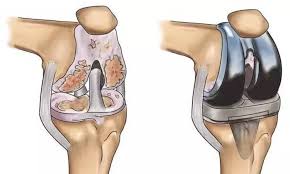

Introduction Robotic knee replacement in Rajnandgaon is redefining the treatment …

Introduction Robotic knee replacement in Raipur is an advanced orthopedic …

Introduction Robotic knee replacement in Raigarh is an advanced orthopedic …

Introduction Robotic knee replacement in Narayanpur is an advanced surgical …